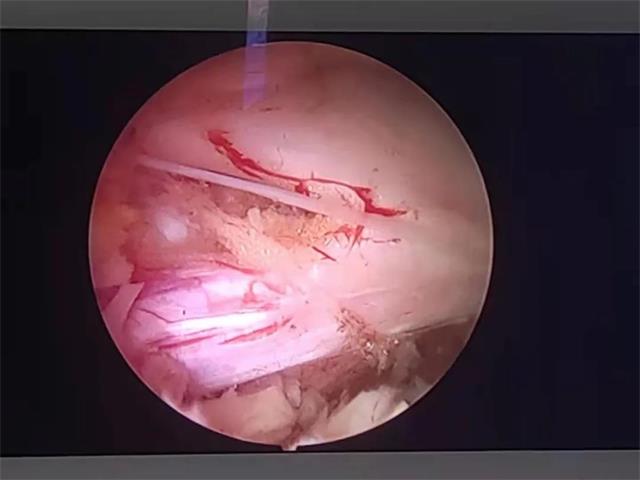

术中同侧神经根显露

术中对侧减压神经根显露